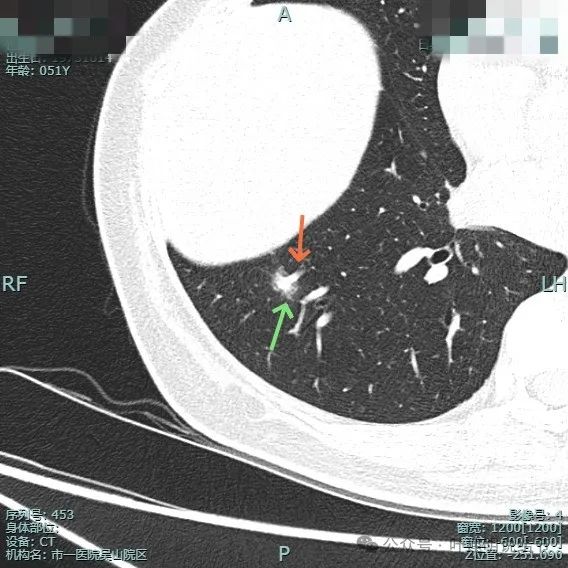

右下病灶混合密度,整体轮廓较清,但瘤肺边界欠清晰。

实性成分占比高,边缘看上去有晕似的,边上有明显血管走行。也有细支气管可见。

实性部分或整体病灶缺乏收缩力,膨胀感也不明显。瘤肺边界欠清晰,感觉有一圈晕。

晕征上图更明显,进入的血管未见明显异常增粗,略显弯曲。